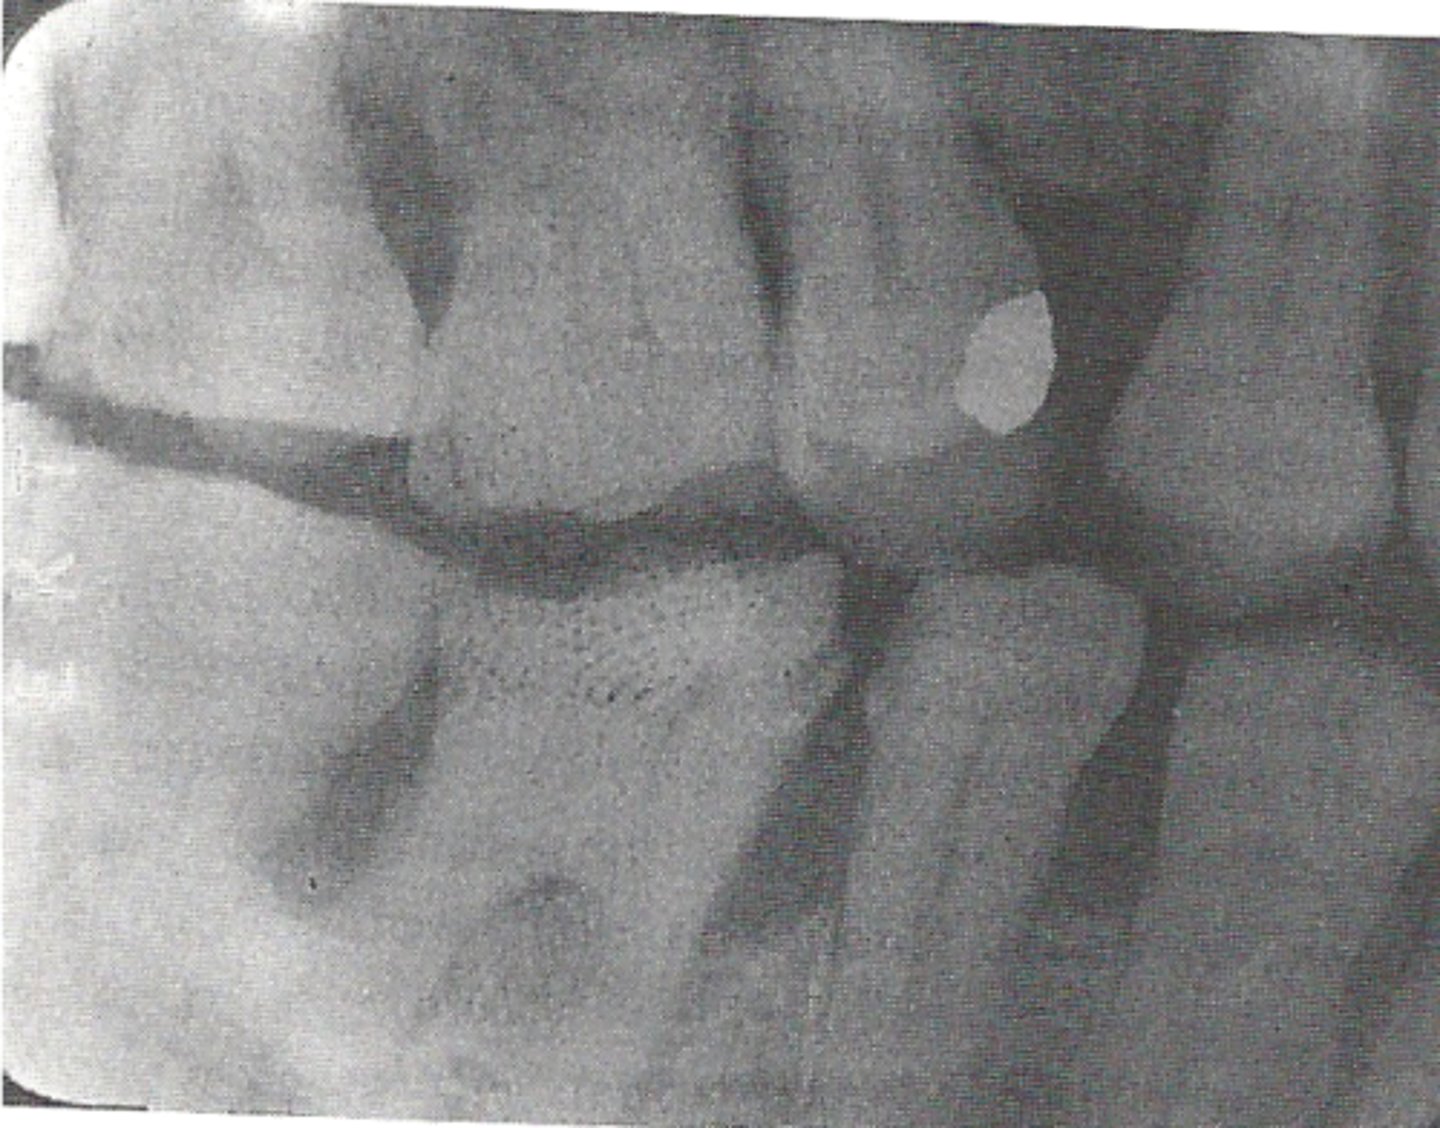

cause film to be too light, fogged, or tinted brown

exhausted fixer pictured